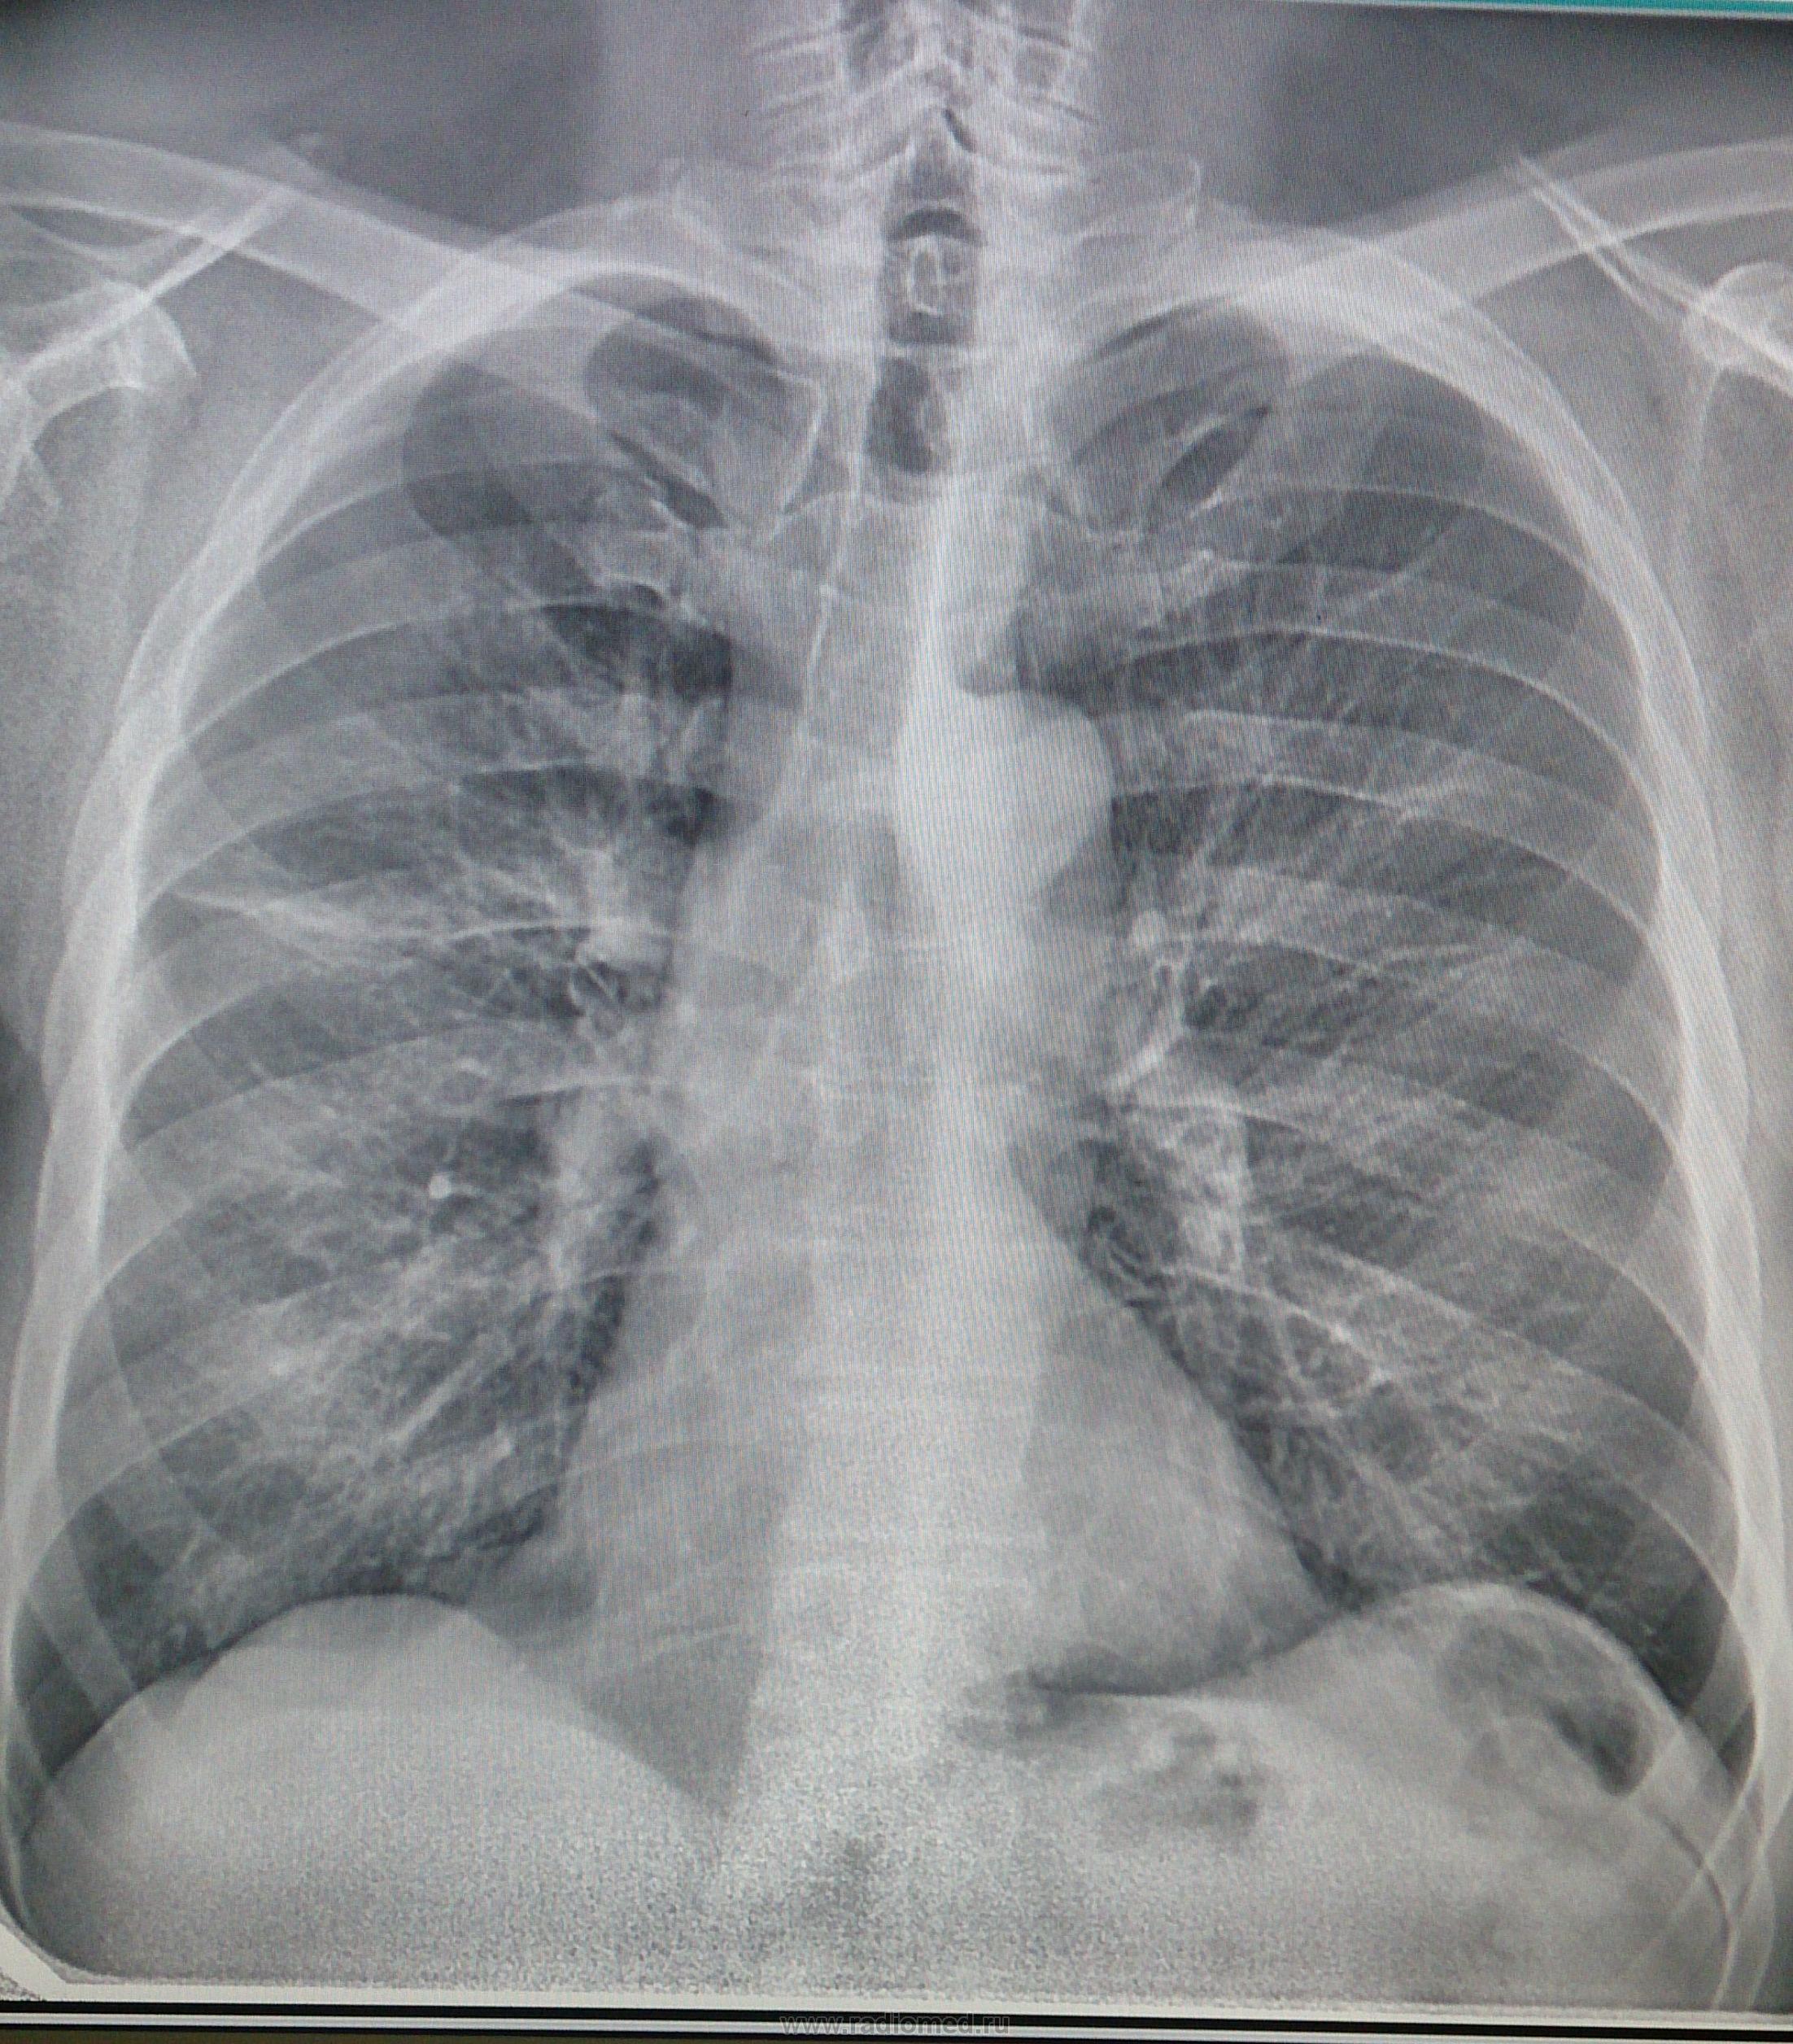

Коронавирус пневмония рентген

Рентген легких пневмония коронавирус

Коронавирус пневмония рентген

Рентген легких пневмония коронавирус

Рентген легких пневмония covid19

Фото рентгеновских снимков поражения легких при COVID-19

На фотографиях рентгеновских снимков видно, как вирус воздействует на легочную ткань. Характерные признаки поражения легких включают пятна, инфильтраты и наличие жидкости внутри легочных альвеол.

Фото рентгеновских снимков помогают врачам и специалистам визуально определить степень поражения легких и принять соответствующие меры лечения и поддержки пациента.